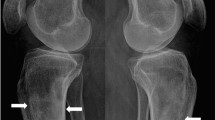

X-rays of the pelvis, right femur, and right knee were performed to investigate possible causes of the reported migratory arthralgia. Two osteolytic lesions were detected in the right distal femur and in the medial aspect of the lesser trochanter of the right proximal femur, which were initially suspected to be incidentally detected bone metastases. Both lesions were radiolucent, irregular and ill defined. No cortical destruction or soft tissue mass was observed. No other abnormalities could be observed (Fig. 1a–c).

X-rays of the right knee and hip (a–c) and CT thorax and abdomen in bone window (d–j). a, b Coronal and sagittal views of the knee joint reveal an osteolytic lesion in the distal third of the femur (arrow). c Coronal view of the hip joint and proximal femur reveals an osteolytic lesion in the medial aspect of the lesser trochanter (arrow). Coronal (d, e, j), sagittal (f–h) and axial (i) views show multiple osteolytic lesions (arrows) of the right and left iliac bone, right femur, right scapula and axillary part of the seventh left rib without and with (circle) cortical breakthrough and associated soft tissue masses